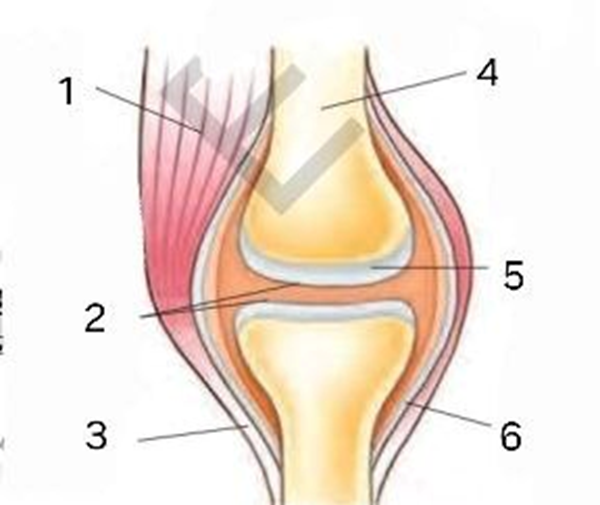

2-topshiriq. Quyidagi rasmda tizza bo’g’imining tuzilishi –“structure of the knee joint” berilgan. Tizza bo’g’imini hosil qilgan bo’limlarning inglizcha nomini yozing.